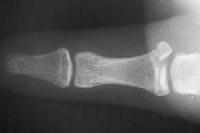

The typical posture is ulnar deviation of the thumb at the metacarpophalangeal joint:

Click for larger image

and another patient..